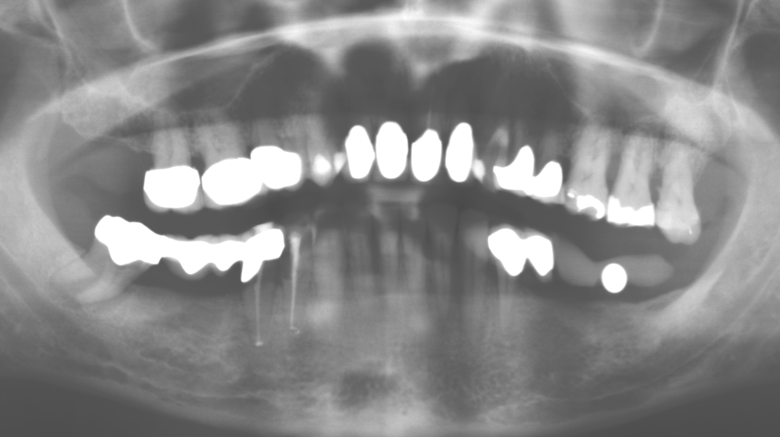

Fig. 1: Panoramic radiograph of initial situation in 2004.

A 52-year-old patient presented in our clinic for the first time in 2004 following tooth loss in the third quadrant, expressing a desire for a new prosthetic restoration. Periodontal and radiological diagnostics revealed the need for extensive periodontological treatment. In addition, teeth 48, 28 and 27 were attributed a very poor prognosis and were subsequently extracted (Fig. 1). Following the successfully completed, systematic periodontological treatment, a fixed dental implant was inserted with the introduction of five implants in tooth regions 35, 36, 37, 46 and 47. Prosthetic treatment of the natural teeth was effected with veneered zirconium dioxide ceramic crowns; the implants were composed of two-piece, individual zirconium dioxide abutments and similarly veneered crowns made of a zirconium dioxide ceramic (Cercon base colored, Dentsply Sirona Lab). Definitive insertion of the prosthetic restoration occurred in 2005.

Fig. 3: Panoramic radiograph after ten years with implants.